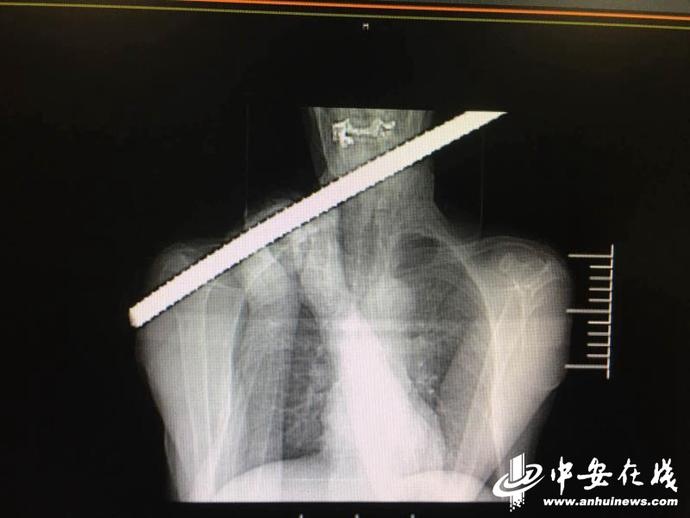

惊险!肥东一务工师傅被1米多长钢筋贯通颈部

图片尺寸690x518